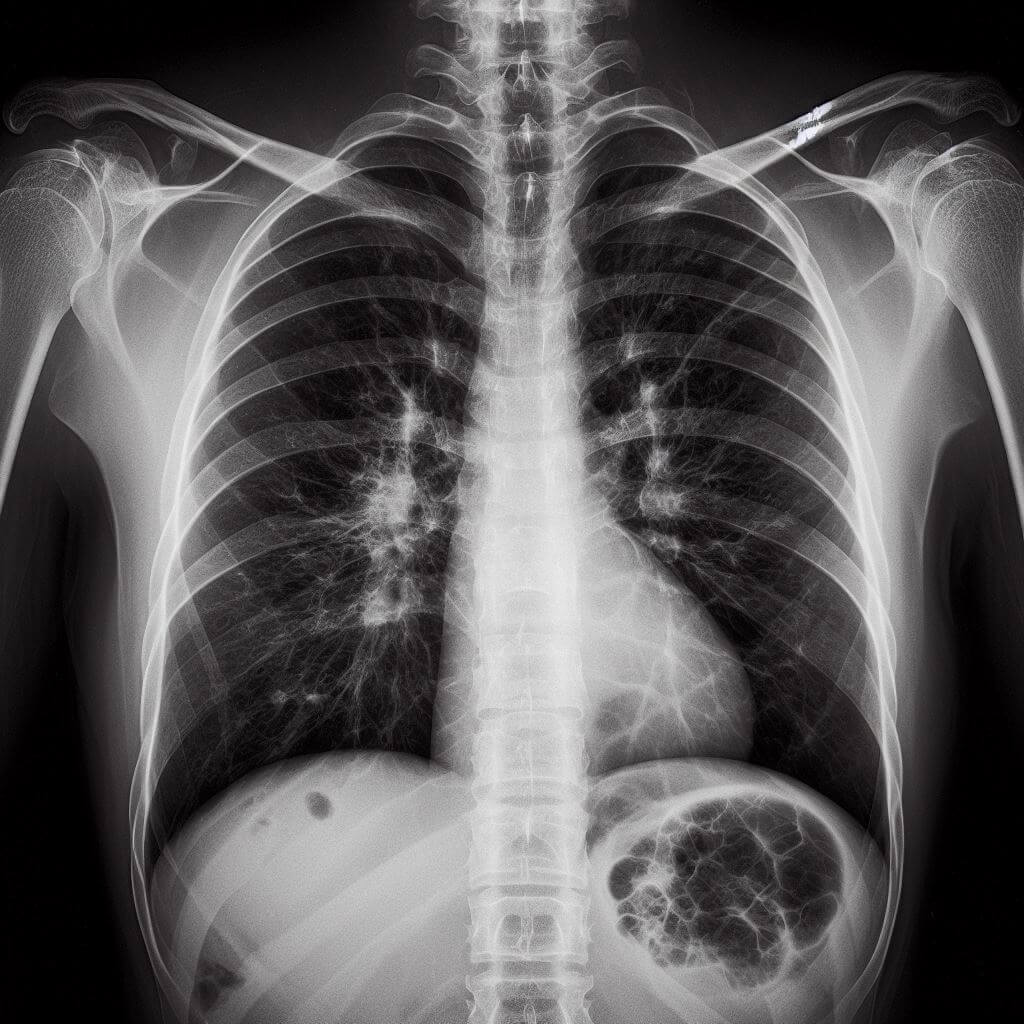

폐결핵은 결핵균(Myobacterium tuberculosis)에 의해 발생하는 전염성 질환으로, 주로 폐에 영향을 미칩니다. 그러나 결핵균은 폐 외의 다른 기관에도 영향을 줄 수 있습니다. 초기에는 증상이 경미하거나 전혀 나타나지 않을 수 있지만, 적절한 치료를 받지 않으면 질병이 진행되어 심각한 건강 문제를 일으킬 수 있습니다. 다음은 폐결핵의 주요 증상들입니다:

기침 시 피가 섞여 나오는 현상(객혈): 결핵이 진행되면서 폐 조직이 손상되어 기침할 때 피가 나올 수 있습니다.